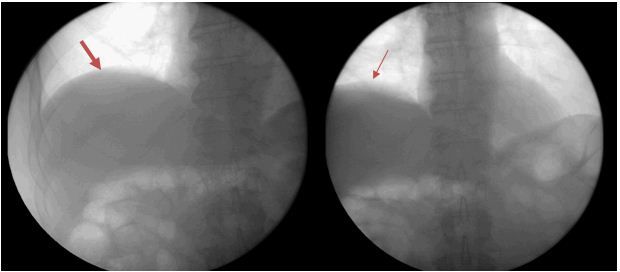

As workup for his dyspnea, the patient underwent pulmonary function testing, which showed a restrictive type of lung disease. A chest radiograph revealed an elevated right hemidiaphragm (Figure 1), which was confirmed by a CT scan (Figure 2). This raised the possibility of right phrenic nerve paralysis as the cause of his symptoms. There was no movement of the right hemidiaphragm observed during a sniff test, (Figure 3) which confirmed the diagnosis.

Figure 3.

Fluoroscopy indicates lack of diaphragm movement during a sniff test.

(Arrows point to the diaphragm.)